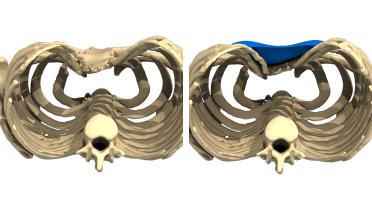

La tecnica di impianto su misura è una tecnica chirurgica minore che consiste nel riempire la concavità creata dal Pectus con un impianto personalizzato. Si tratta di un intervento rapido, a basso rischio, con un risultato immediato e una breve convalescenza.

In questa pagina, troverà i risultati di questa operazione a seconda del tipo di Pectus : mediale, asimmetrico, più o meno profondo o lungo.

Tipo 1 : Mediano, profondo e simmetrico,